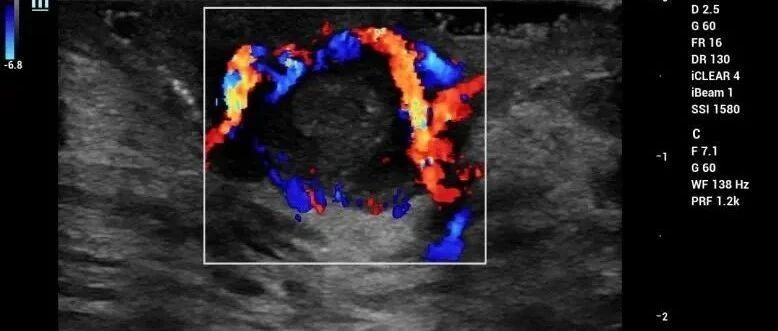

急诊床旁彩超诊断腹主动脉瘤破裂 2 例 丁香园超声时间 · 公众号 · 医学 · 1 年前 · |